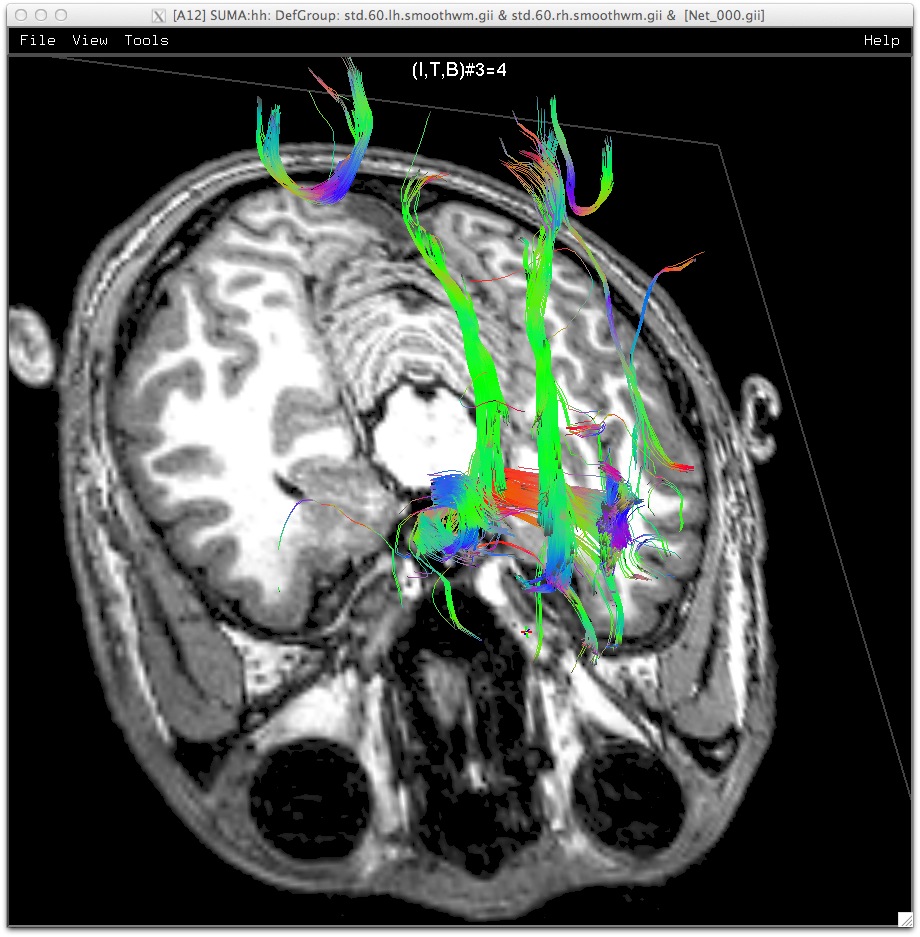

Tracts going though an interactively positioned mask in the midbrain area. Slice transparency set to 8. (link)